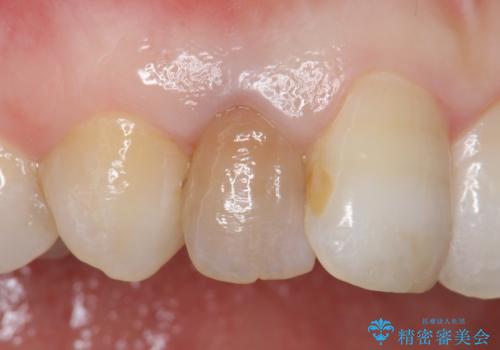

- 右上2番目の歯の変色が気になるといらっしゃった方の症例です。

再根管治療終了後、オールセラミッククラウンによる補綴を行いました。